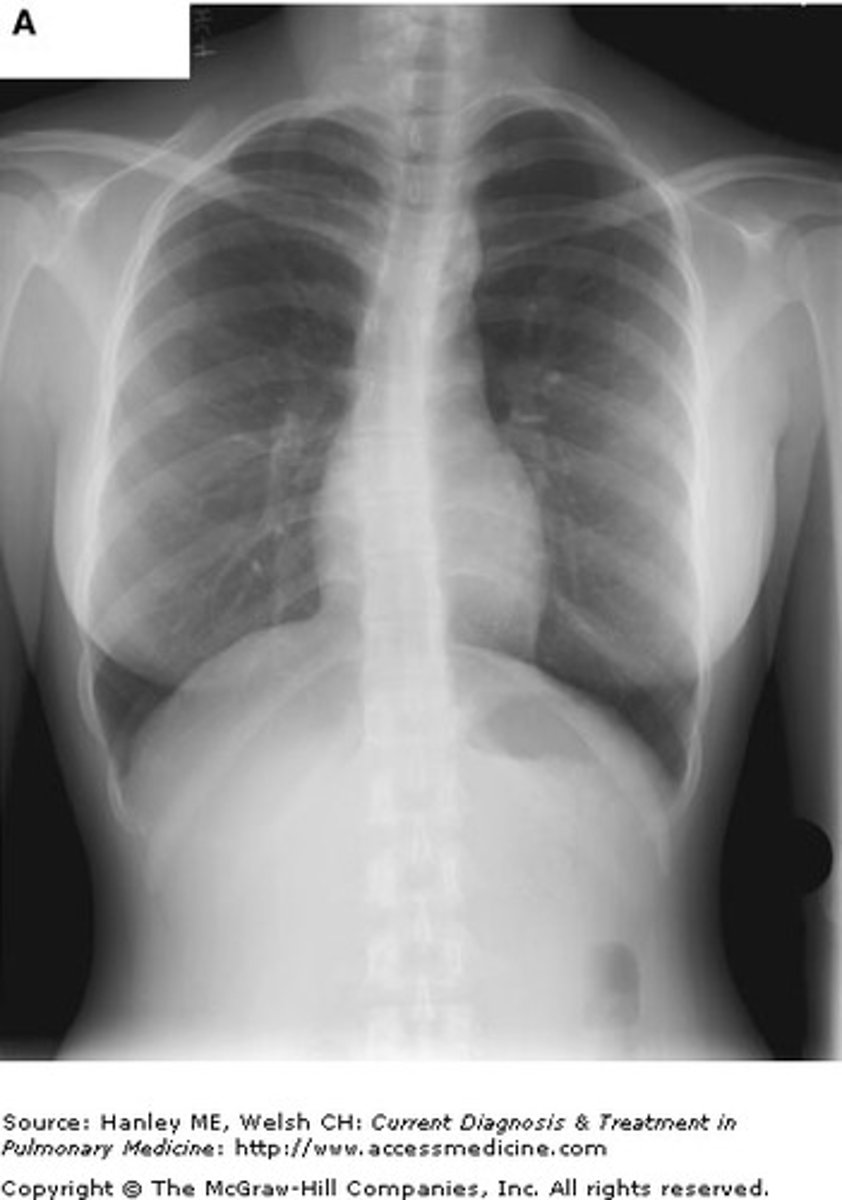

A 24-year-old female HIV-positive patient, who is not currently on medication, presents to the emergency department with acute dyspnea, tachycardia, fever, nonproductive cough, and a room air oxygen saturation of 92%. She admits feeling poorly for the past five days. A physical exam reveals bilateral basilar crackles. An x-ray reveals the image shown. What is the most likely causative organism of this clinical picture?

Pneumocystis is an opportunistic fungal infection of immunocompromised patients, most frequently seen in patients with untreated HIV/AIDS. Patients often present with fever, dyspnea, a nonproductive cough, decreased arterial oxygen pressure, and tachycardia. Lung auscultation may reveal adventitious sounds, but may also be without abnormality. Chest x-ray results classically include bilateral diffuse infiltrates with perihilar involvement. Although the other etiologies are associated with pneumonia, and may be seen in immunocompromised patients, pneumocystis pneumonia occurs in up to 80% of untreated HIV patients and is a leading cause of death.